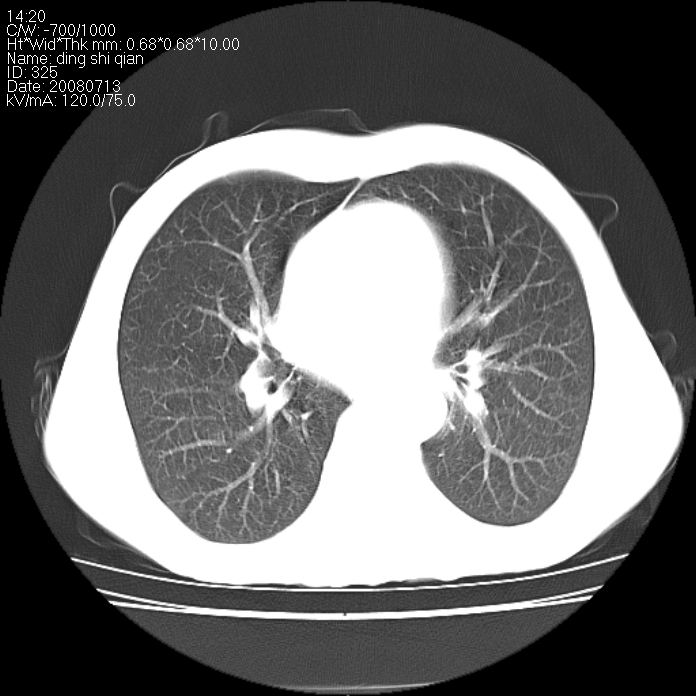

标题: CT14654:男 50岁 近来胸痛 [打印本页]

标题: CT14654:男 50岁 近来胸痛

右侧上肺块状软组织影,浅分叶,边缘毛刺证,与胸膜粘连,考虑:周围性肺癌

右肺上叶周围型肺癌可能性大。

右侧上肺块状软组织影,浅分叶,边缘毛刺证,与胸膜粘连,考虑:周围性肺癌!支持!

典型右肺周围型肺癌

首先考虑周围性肺癌,建议强化或穿刺明确

考虑: 右肺上叶周围型肺癌可能性大.

右肺上叶周围型肺癌。